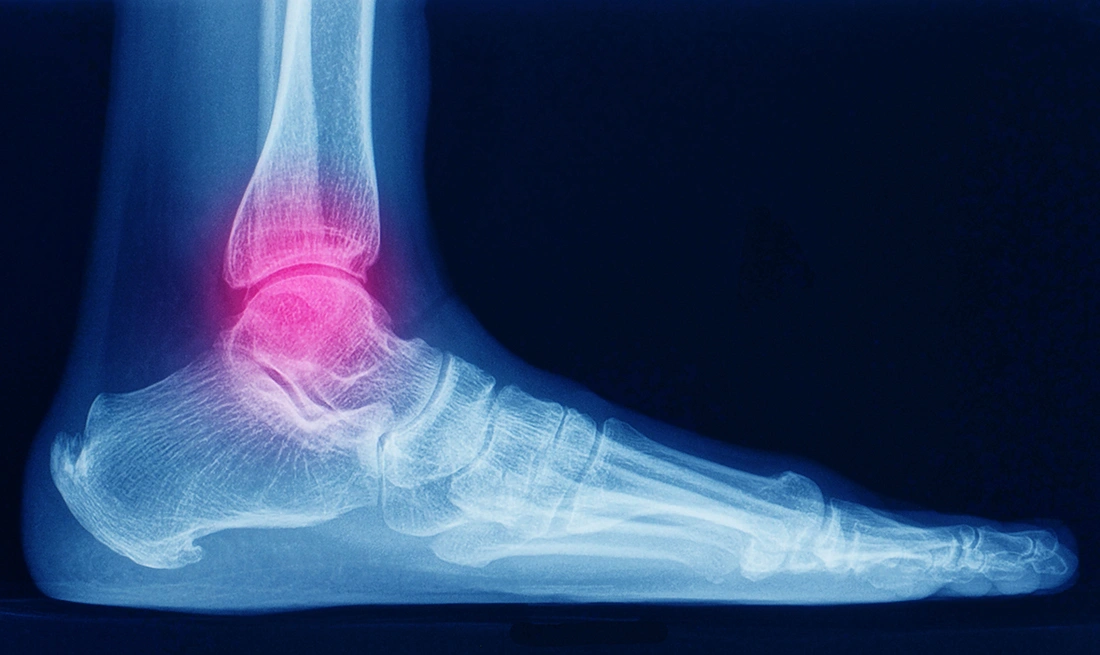

Ankle pain is common after a twist, fall or increased physical activity, and in many cases it improves with rest and simple care. However, persistent symptoms may indicate a need for further evaluation rather than continued rest alone. In some cases, imaging such as X-rays or MRI scans may be used to identify underlying injuries and guide appropriate treatment.

When ankle pain does not improve with rest or when more serious injury is suspected, your ankle specialist may recommend imaging tests to better understand the underlying cause. Each type of imaging provides different information and is selected based on your symptoms and clinical findings.

X-rays

X-rays are usually the first imaging test performed. They are useful for detecting fractures, bone alignment issues and signs of arthritis.